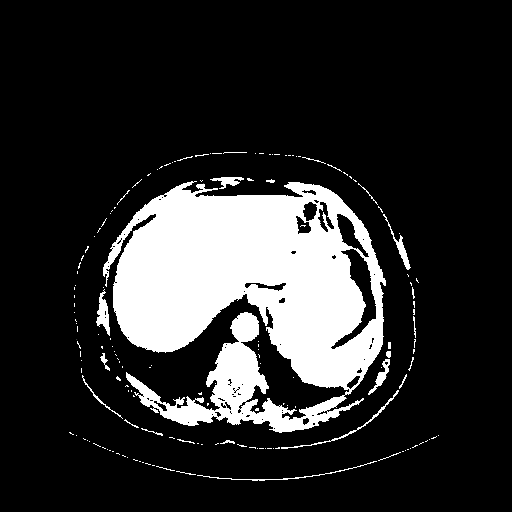

Reconstructed NATIVE CT scan (cycle consistency)

Full window (WL 1023.5, WW 4095 β†’ Low βˆ’1024, High +3071)

Actual HU range: [-1024.0, 3071.0]